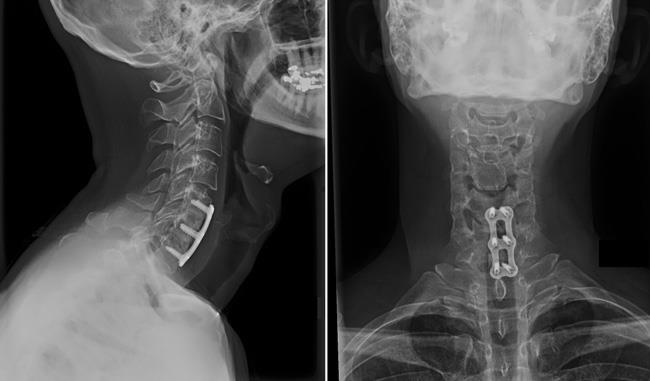

Cervical Lumbar Spondylosis Surgeon In Nashik Surgery. If conservative treatment fails or if neurological symptoms — such as weakness in your arms or legs — worsen, you might need surgery to create more room for your spinal cord and nerve roots. The surgery might involve removing a herniated disk, bone spurs or part of a vertebra.